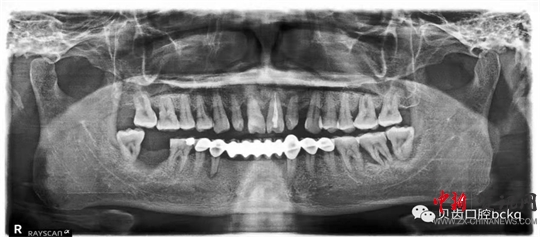

下面這兩張x光片是比較典型的牙周炎的影像資料。該患者的全口所有牙齒都出現(xiàn)了不同程度的松動(dòng);颊攥F(xiàn)在感覺(jué)無(wú)法用牙齒咀嚼。坦白地講,牙周炎發(fā)展到這種程度,很多時(shí)候醫(yī)生也束手無(wú)策了。為了保留更多的牙槽骨,醫(yī)生回不得不拔掉哪些嚴(yán)重松動(dòng)的患牙。